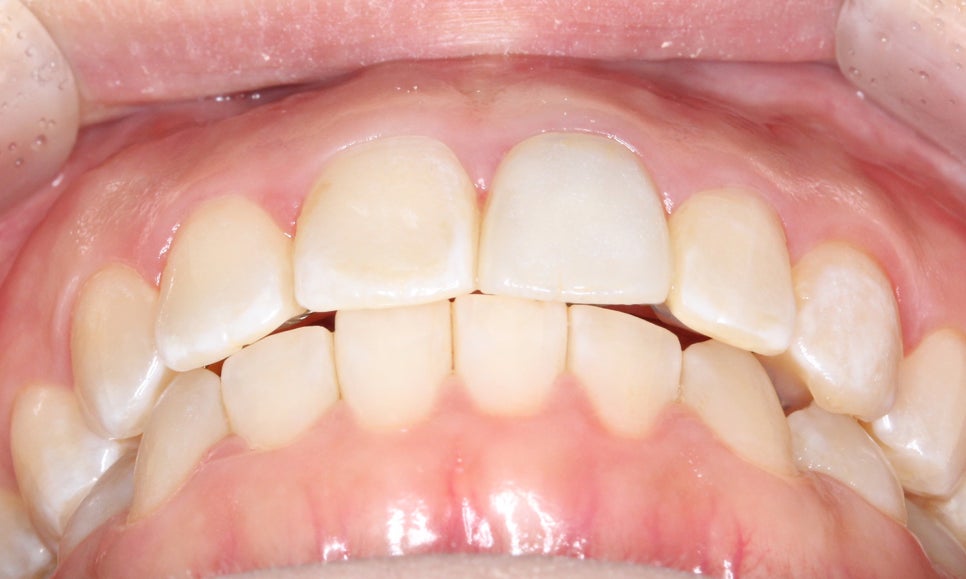

상하악 2D교정 전

2D치과

오늘은 양악교정 case를 송곳니교정

중심으로 소개해드리려고 하는데요,

위의 구내사진을 보시면 사진에서

상악 우측 부분의 송곳니가

덧니처럼 맹출되어 있는 것을 확인할 수 있습니다.

정면에서 보면 치아가 순측으로

뻐드러져 있는 모습인데요,

전체적으로 전치부의 치열이

삐뚤거리고 한쪽 방향으로

치우쳐져 있는 모습입니다.